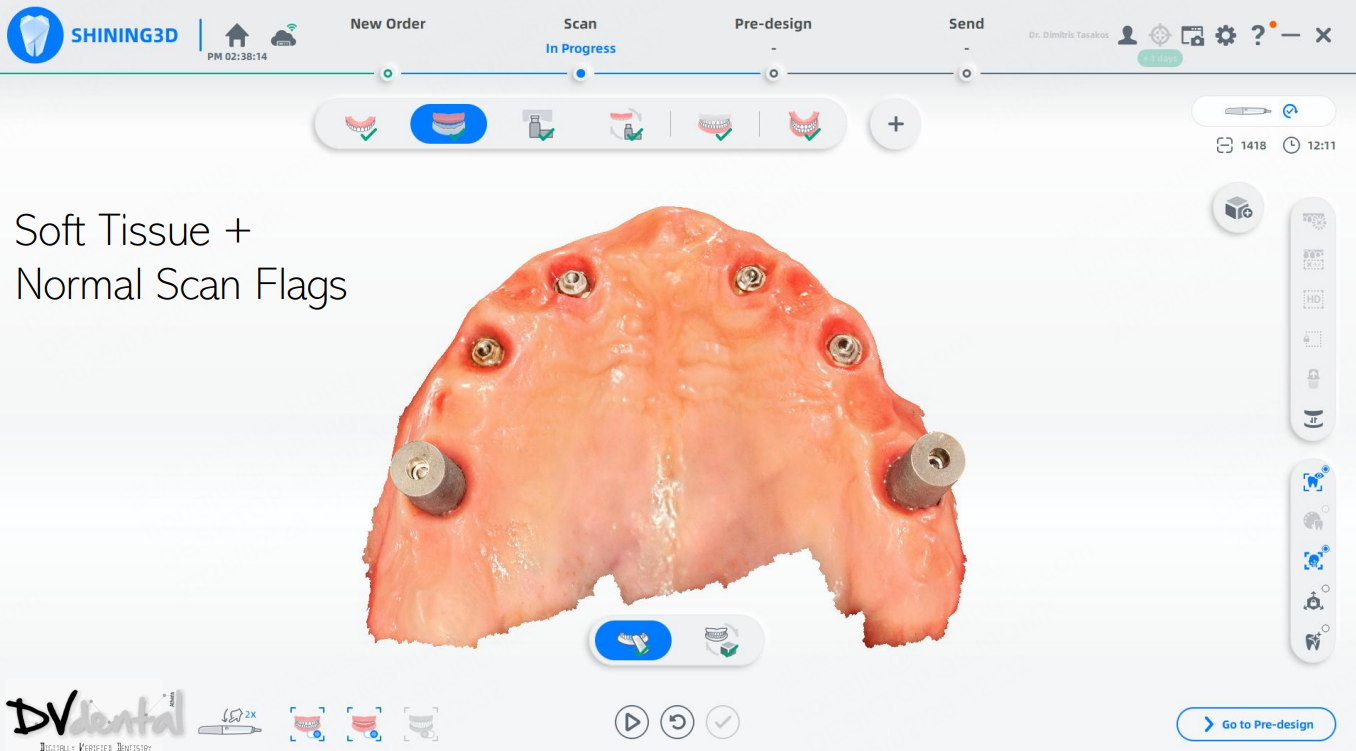

In this case, we encountered a problem: while the MUA of the four anterior implants were compatible with the IPG scan bodies, the two posterior implants were not compatible with the IPG scan bodies. Therefore, we will scan the two posterior implants using normal 3D reconstruction technology (in the soft tissue scan, placing two standard scan bodies on the MUA of the two posterior implants) and then scan the anterior implants with IPG technology (placing the IPG scan bodies on the MUA of the four anterior implants).

Fig 10: Step five, scan the soft tissue and normal scan flags.